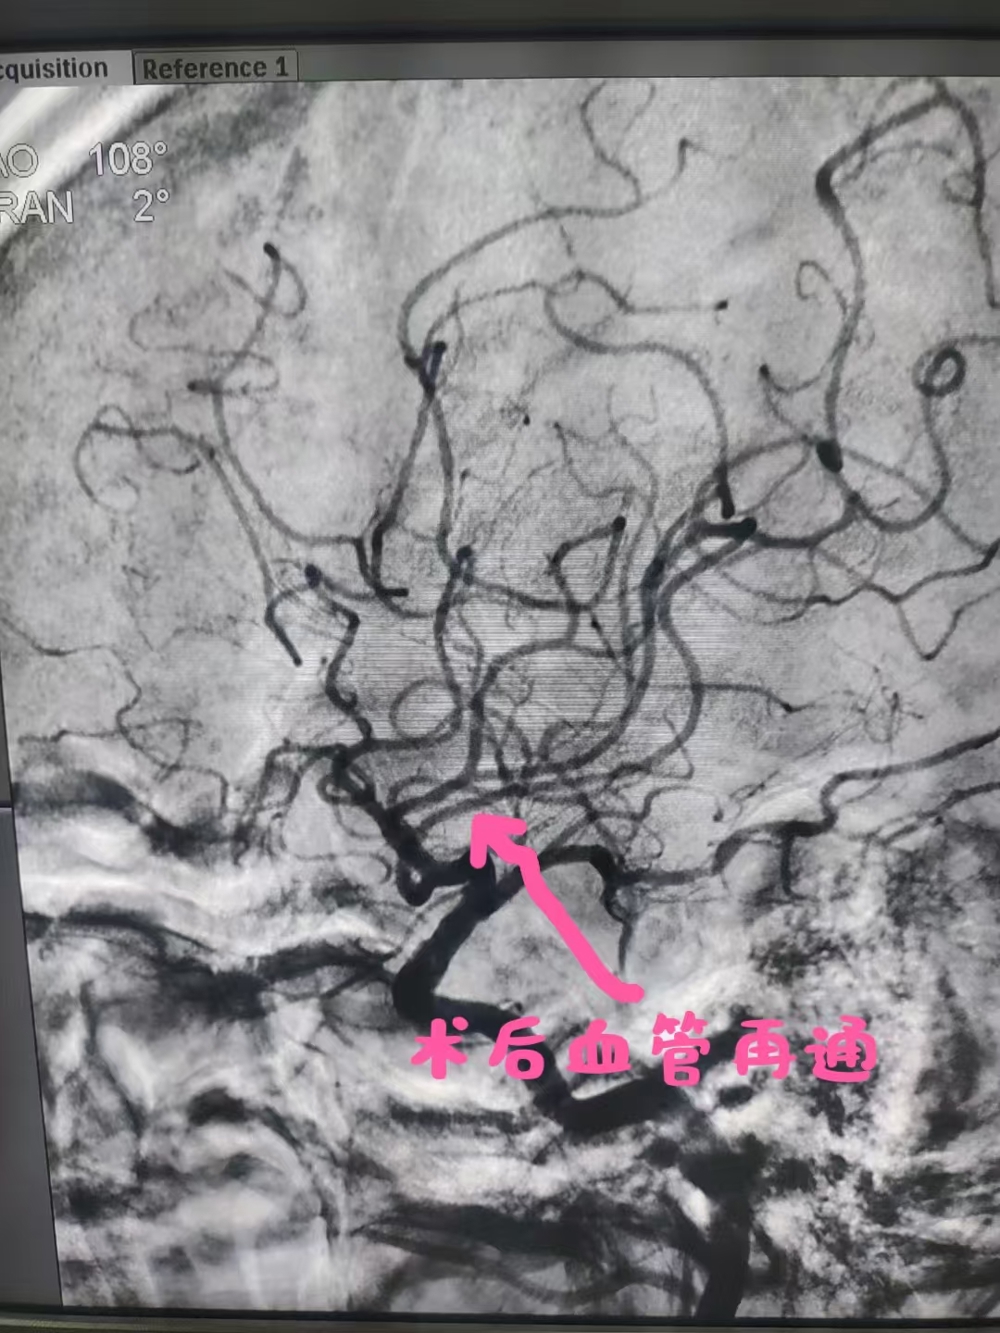

术后大脑中动脉再通

胡华林主任及其介入团队快速制定手术方案。行脑血管造影示:III型主动脉弓右侧大脑中动脉下干栓塞,通过介入取栓55分钟开通了闭塞的右侧大脑中动脉,莫伯伯的右侧大脑中动脉成功恢复了血流再通。手术非常顺利,莫伯伯术后言语恢复清晰,能够自由下床活动,日常生活能自理。胡华林主任针对莫伯伯基础疾病及时调整用药,并叮嘱规律服药和返院复查等相关事宜,术后1周后莫伯伯顺利出院。